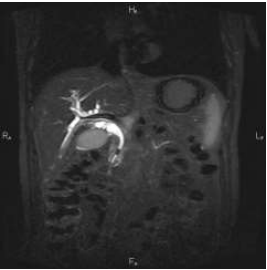

Mulher de 51 anos, portadora de obesidade grau 1 e diabetes mellitus, procura atendimento por queixa de dor

intermitente em hipocôndrio direito há 4 dias, associada à colúria e acolia fecal nas últimas 24 horas. Nega febre. Ao

exame físico, apresenta-se ictérica (2+/4+), com dor à palpação em hipocôndrio direito e Murphy negativo. Exames

laboratoriais: BT 5,2mg/dL (BD 4,3mg/dL), FA 420 U/L, GGT 610 U/L, TGO 86 U/L, TGP 104 U/L, amilase 30 U/L,

lipase 55 U/L, leucometria 8.900/mm

Diante do achado da imagem, qual a conduta mais adequada?